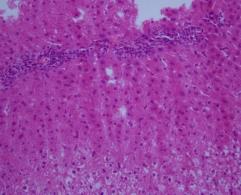

Microscopic examination of liver:

Sections show liver tissue with overall preserved lobular architecture. Portal tracts are within normal limits, containing portal triad and scanty fibrous tissue. Sinusoidal dilatation and congestion is seen. No significant portal or lobular inflammation was seen. Diffuse lipofuscinosis is noted. No cholestasis. No evidence of granuloma or malignancy is seen

Fig. 1: Microscopic examination of male rabbit’s heart, stomach, liver and kidney tissues treated with S. nigra extract